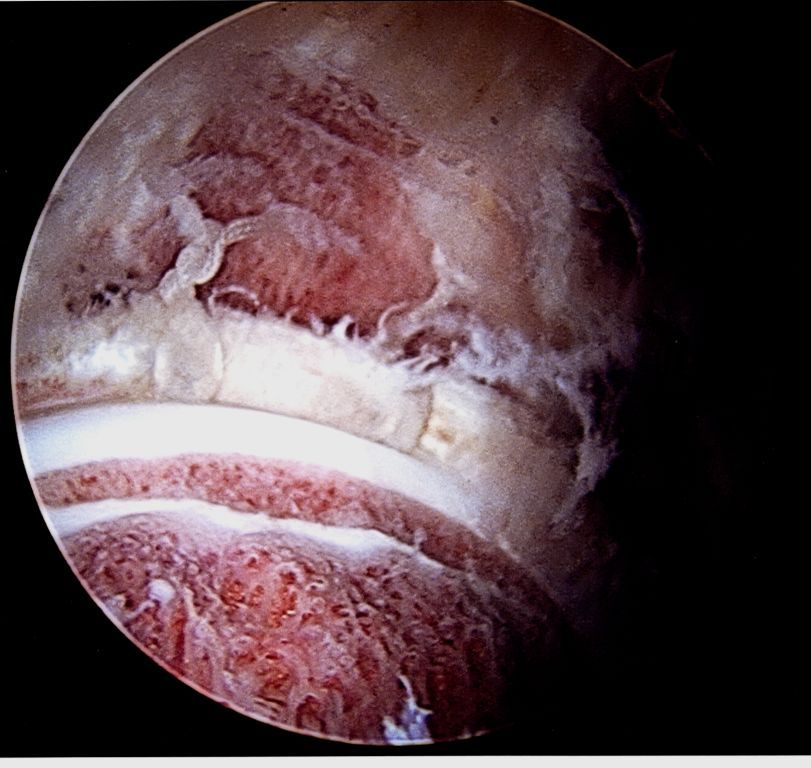

Arthroscopic image after acetabular rim trimming, labral repair with sutures, and femoral neck osteoplasty with open growth plate in the femoral head.

Acetabular rim trimming